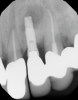

In this case, a dental implant that had been placed 10 years prior was functional, stable, and esthetically acceptable to the patient. However, a significant fistula was present on the facial-apical aspect of the ridge in the maxillary lateral incisor area. This area was painfully sensitive to touch and demonstrated purulence when squeezed. To evaluate the lesion, first, a conventional digital radiograph was acquired, which revealed an apical radiolucency at the apex of the implant (Figure 1). Further analysis using cone-beam computed tomography (CBCT) demonstrated a fistula from that site to the oral environment (Figure 2). Treatment options were discussed, including removal of the implant, followed by grafting, a healing period, and replacement of the implant and implant-retained crown. If this option was selected, a transitional appliance would need to be created. Another option was to attempt to salvage the implant and implant crown by treating the infection and grafting the site to create a new boney wall and eliminate the fistula. Ultimately, the patient accepted this option to attempt to salvage the fixture and crown.

(2.) Preoperative CBCT analysis demonstrating a fistula from the site of the radiolucency to the oral environment.

Figure 2